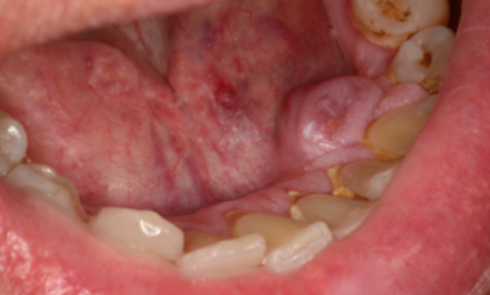

Article réservé à nos abonnés Rien que du pur MALT ?

Motif de la consultation. Patiente de 19 ans venue consulter pour des douleurs dentaires en rapport avec des caries. Histoire...